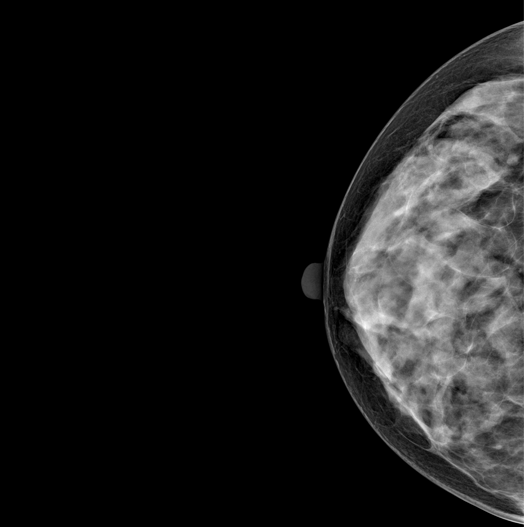

SYNTHESIZED 2D

HESTIA supports "Synthetic 2D" that generates 2D images only by tomography shooting without additional 2D shooting.